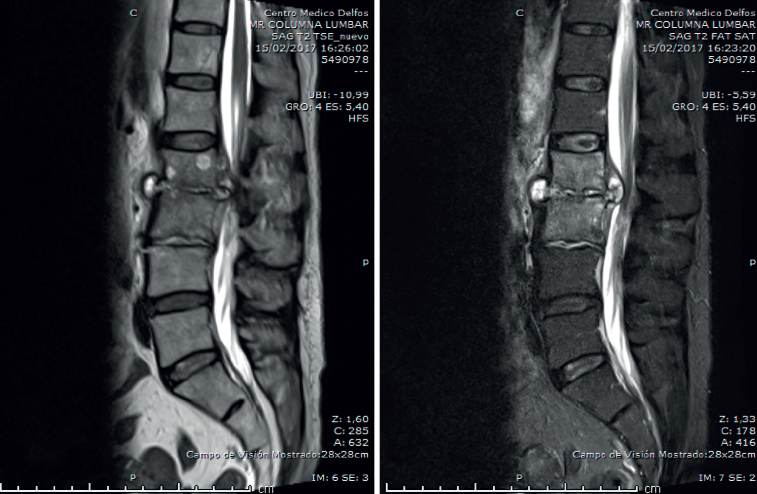

- Resonancia magnética (RM) lumbar (Figura 2): sagitales con secuencias T2 y STIR. Espondilodiscitis aguda con absceso en canal raquídeo y prevertebral.